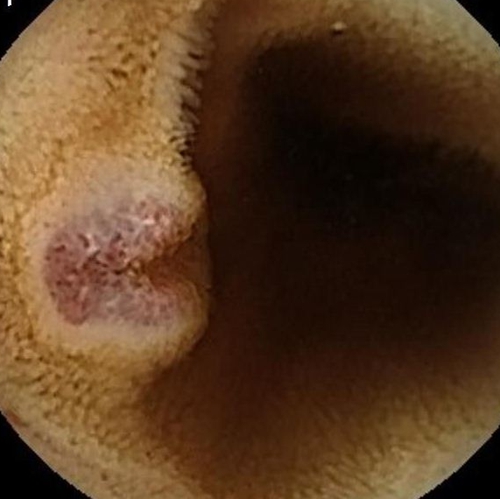

為了進一步查找病因,兒童消化內(nèi)科醫(yī)生決定利用“胃鏡+結(jié)腸鏡+膠囊內(nèi)鏡”三鏡聯(lián)合的方式進行檢查。檢查結(jié)果觸目驚心!

浩浩的胃、小腸及結(jié)腸內(nèi)有多發(fā)藍色大皰樣隆起,大大小小的有20多個,就好像在胃腸內(nèi)灑落了許多藍莓。尤其是小腸病變尤其明顯,最大顆幾乎堵塞了腸腔的一半。

兒童消化內(nèi)科急請血管瘤診療??茖<視\,結(jié)合既往病史,最終診斷為“藍色橡皮皰痣綜合征”。這些藍色大皰樣隆起其實是消化道靜脈瘤,間斷有靜脈瘤破裂出血,浩浩的重度貧血正是由于本病引起的長期消化道慢性出血所致。至此,困擾浩浩一家長達2年之久的反復(fù)貧血之謎得以解開。

另一個常見臨床表現(xiàn)就是消化道血管瘤,可累及整個消化道,最常見于小腸,其次是結(jié)腸和胃,這些血管瘤會引起不同程度的消化道出血,從而導(dǎo)致患者出現(xiàn)長期貧血。